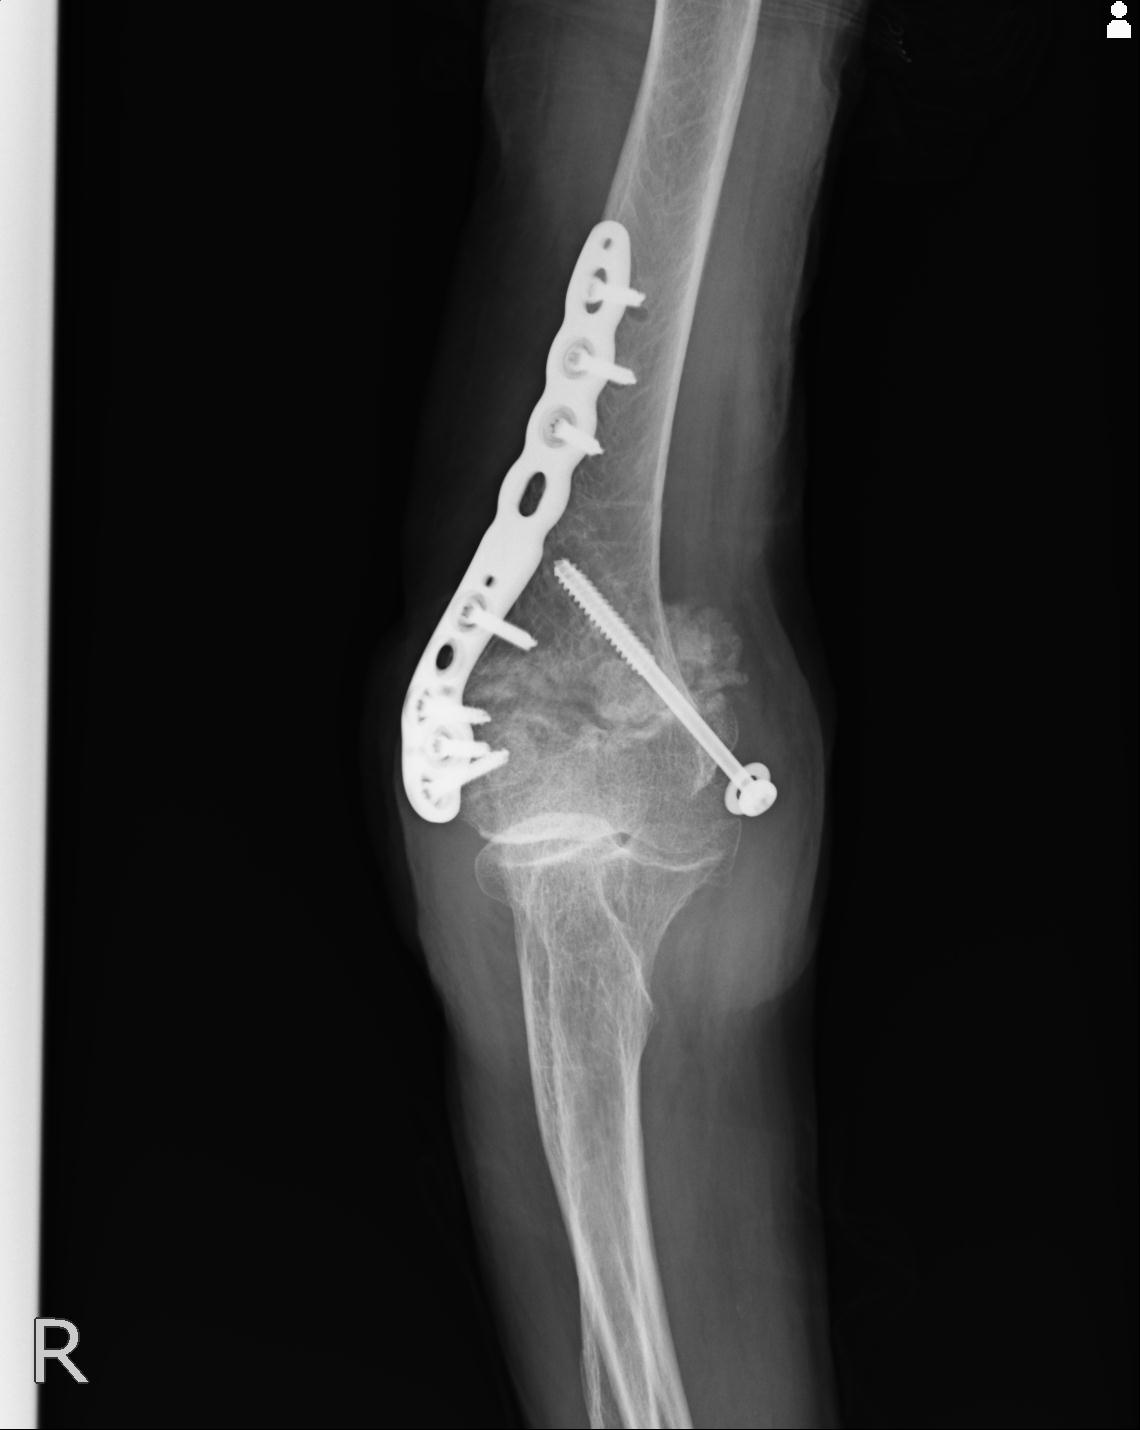

102755 1/4 2R 1/15 2R 右足関節 68歳女性 右三果脱臼骨折